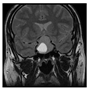

3.1. Datasets